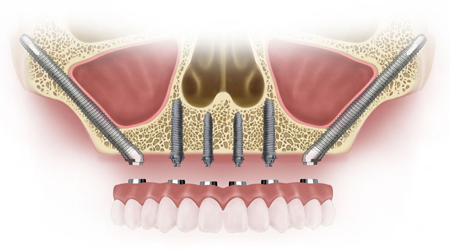

ALL- ON -4 FOR LESS BONE

Upper Jaw/Lower Jaw (Per Jaw)

Technique INR US

4 NOBEL BIOCARE Implants including 2 ANGULATED Implants + IMMEDIATE Provisional Denture + Final Fixed Titanium Hybrid Denture of 12-14 Teeth 350000 5400

4 NOBEL BIOCARE Implants including 2 ANGULATED Implants + IMMEDIATE Provisional Denture + Final Fixed PROCERA Implant Bridge Denture of 12-14 ZIRCONIA Ceramic Crown 500000 7600

ALL- ON -4 WITH ZYGOMA IMPLANTS (FOR MINIMAL BONE)

Upper Jaw

4 NOBEL BIOCARE Implants including 2 ZYGOMA Implants + IMMEDIATE Provisional Denture + Final Fixed TITANIUM HYBRID Denture of 12-14 Teeth 650000 10000

4 NOBEL BIOCARE Implants (QUAD ZYGOMA)+ IMMEDIATE Provisional Denture + Final Fixed TITANIUM HYBRID Denture of 12-14 Teeth 800000 12300